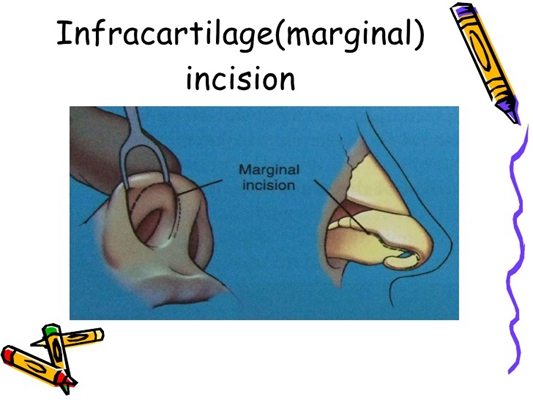

鼻中隔彎曲手術圖解 (42)

鼻中隔彎曲手術圖解 (41)

鼻中隔彎曲手術圖解 (30)

鼻中隔彎曲手術圖解 (31)